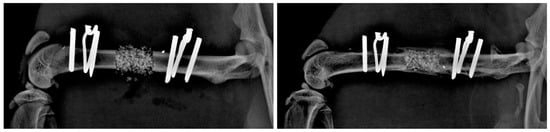

- Gulabi, D.; Erdem, M.; Cecen, G.S.; Avci, C.C.; Saglam, N.; Saglam, F. Ilizarov Fixator Combined With an Intramedullary Nail for Tibial Nonunions With Bone Loss: Is It Effective? Clin. Orthop. Relat. Res. 2014, 472, 3892–3901. [Google Scholar] [CrossRef]